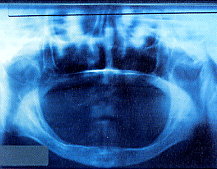

無歯顎のレントゲン写真

インプラント4本を埋入

インプラント埋入後のレントゲン写真